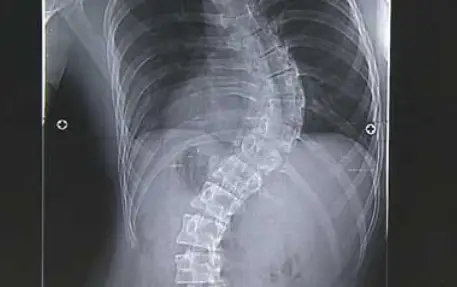

우리 몸의 척추는 아시다시피 휘어져 있습니다. 어느 정도의 굽은 상태이기 때문에 비정상은 아닙니다. 하지만 옆면이 아닌 정면에서 보았을 때 척추가 옆으로 휘어져 있다면 문제가 되며 이를 척추 변형이라고 합니다.

척추 측만증이란 바로 척추가 똑바로 서지 못하고 옆으로 휘어져 있는 상태를 말합니다. 단순하게 휘어져 있는 상태가 아니라 척추뼈가 회전이 되어 옆에서 보았을 때 3차원적인 변형을 말합니다. 그래서 심하게 되면 몸이 앞으로 굽어져 휘어지게 됩니다.